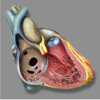

atrial septal defect (ASD)

ventricular septal defect (VSD)

atrioventricular septal defect (AVSD)